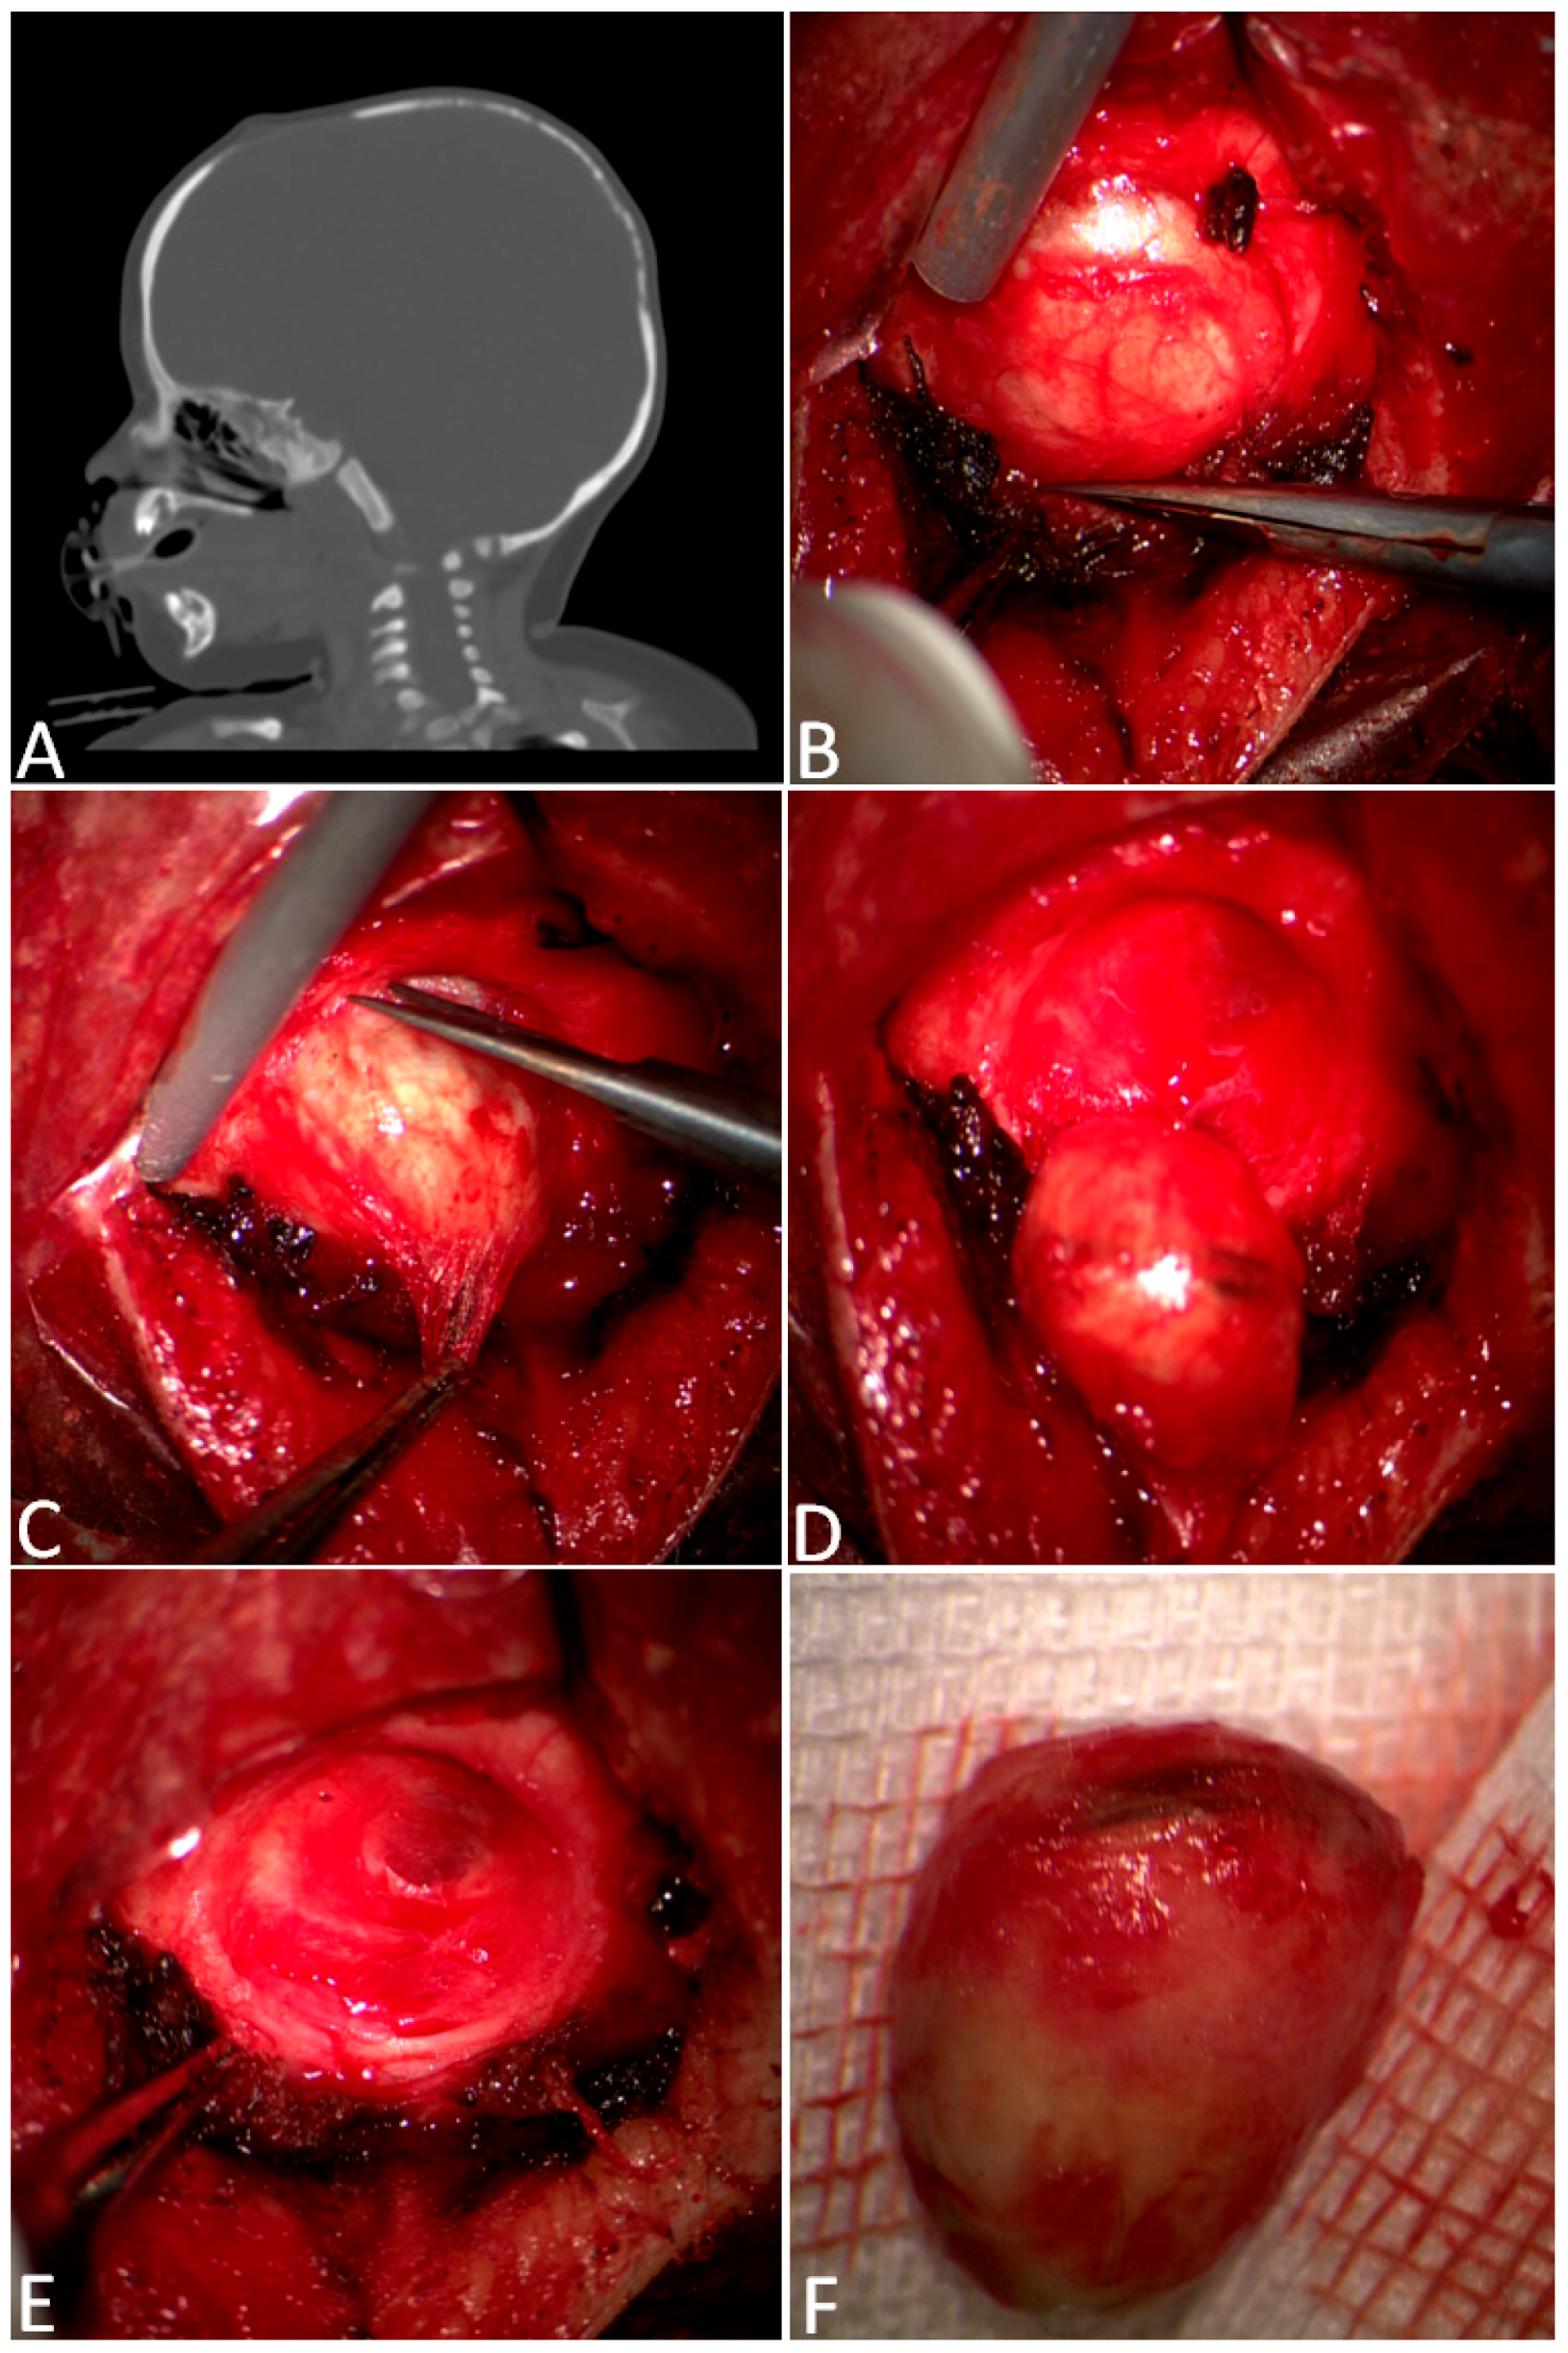

3.3. A Complex Case: Melanocytic Neuroectodermal Tumor